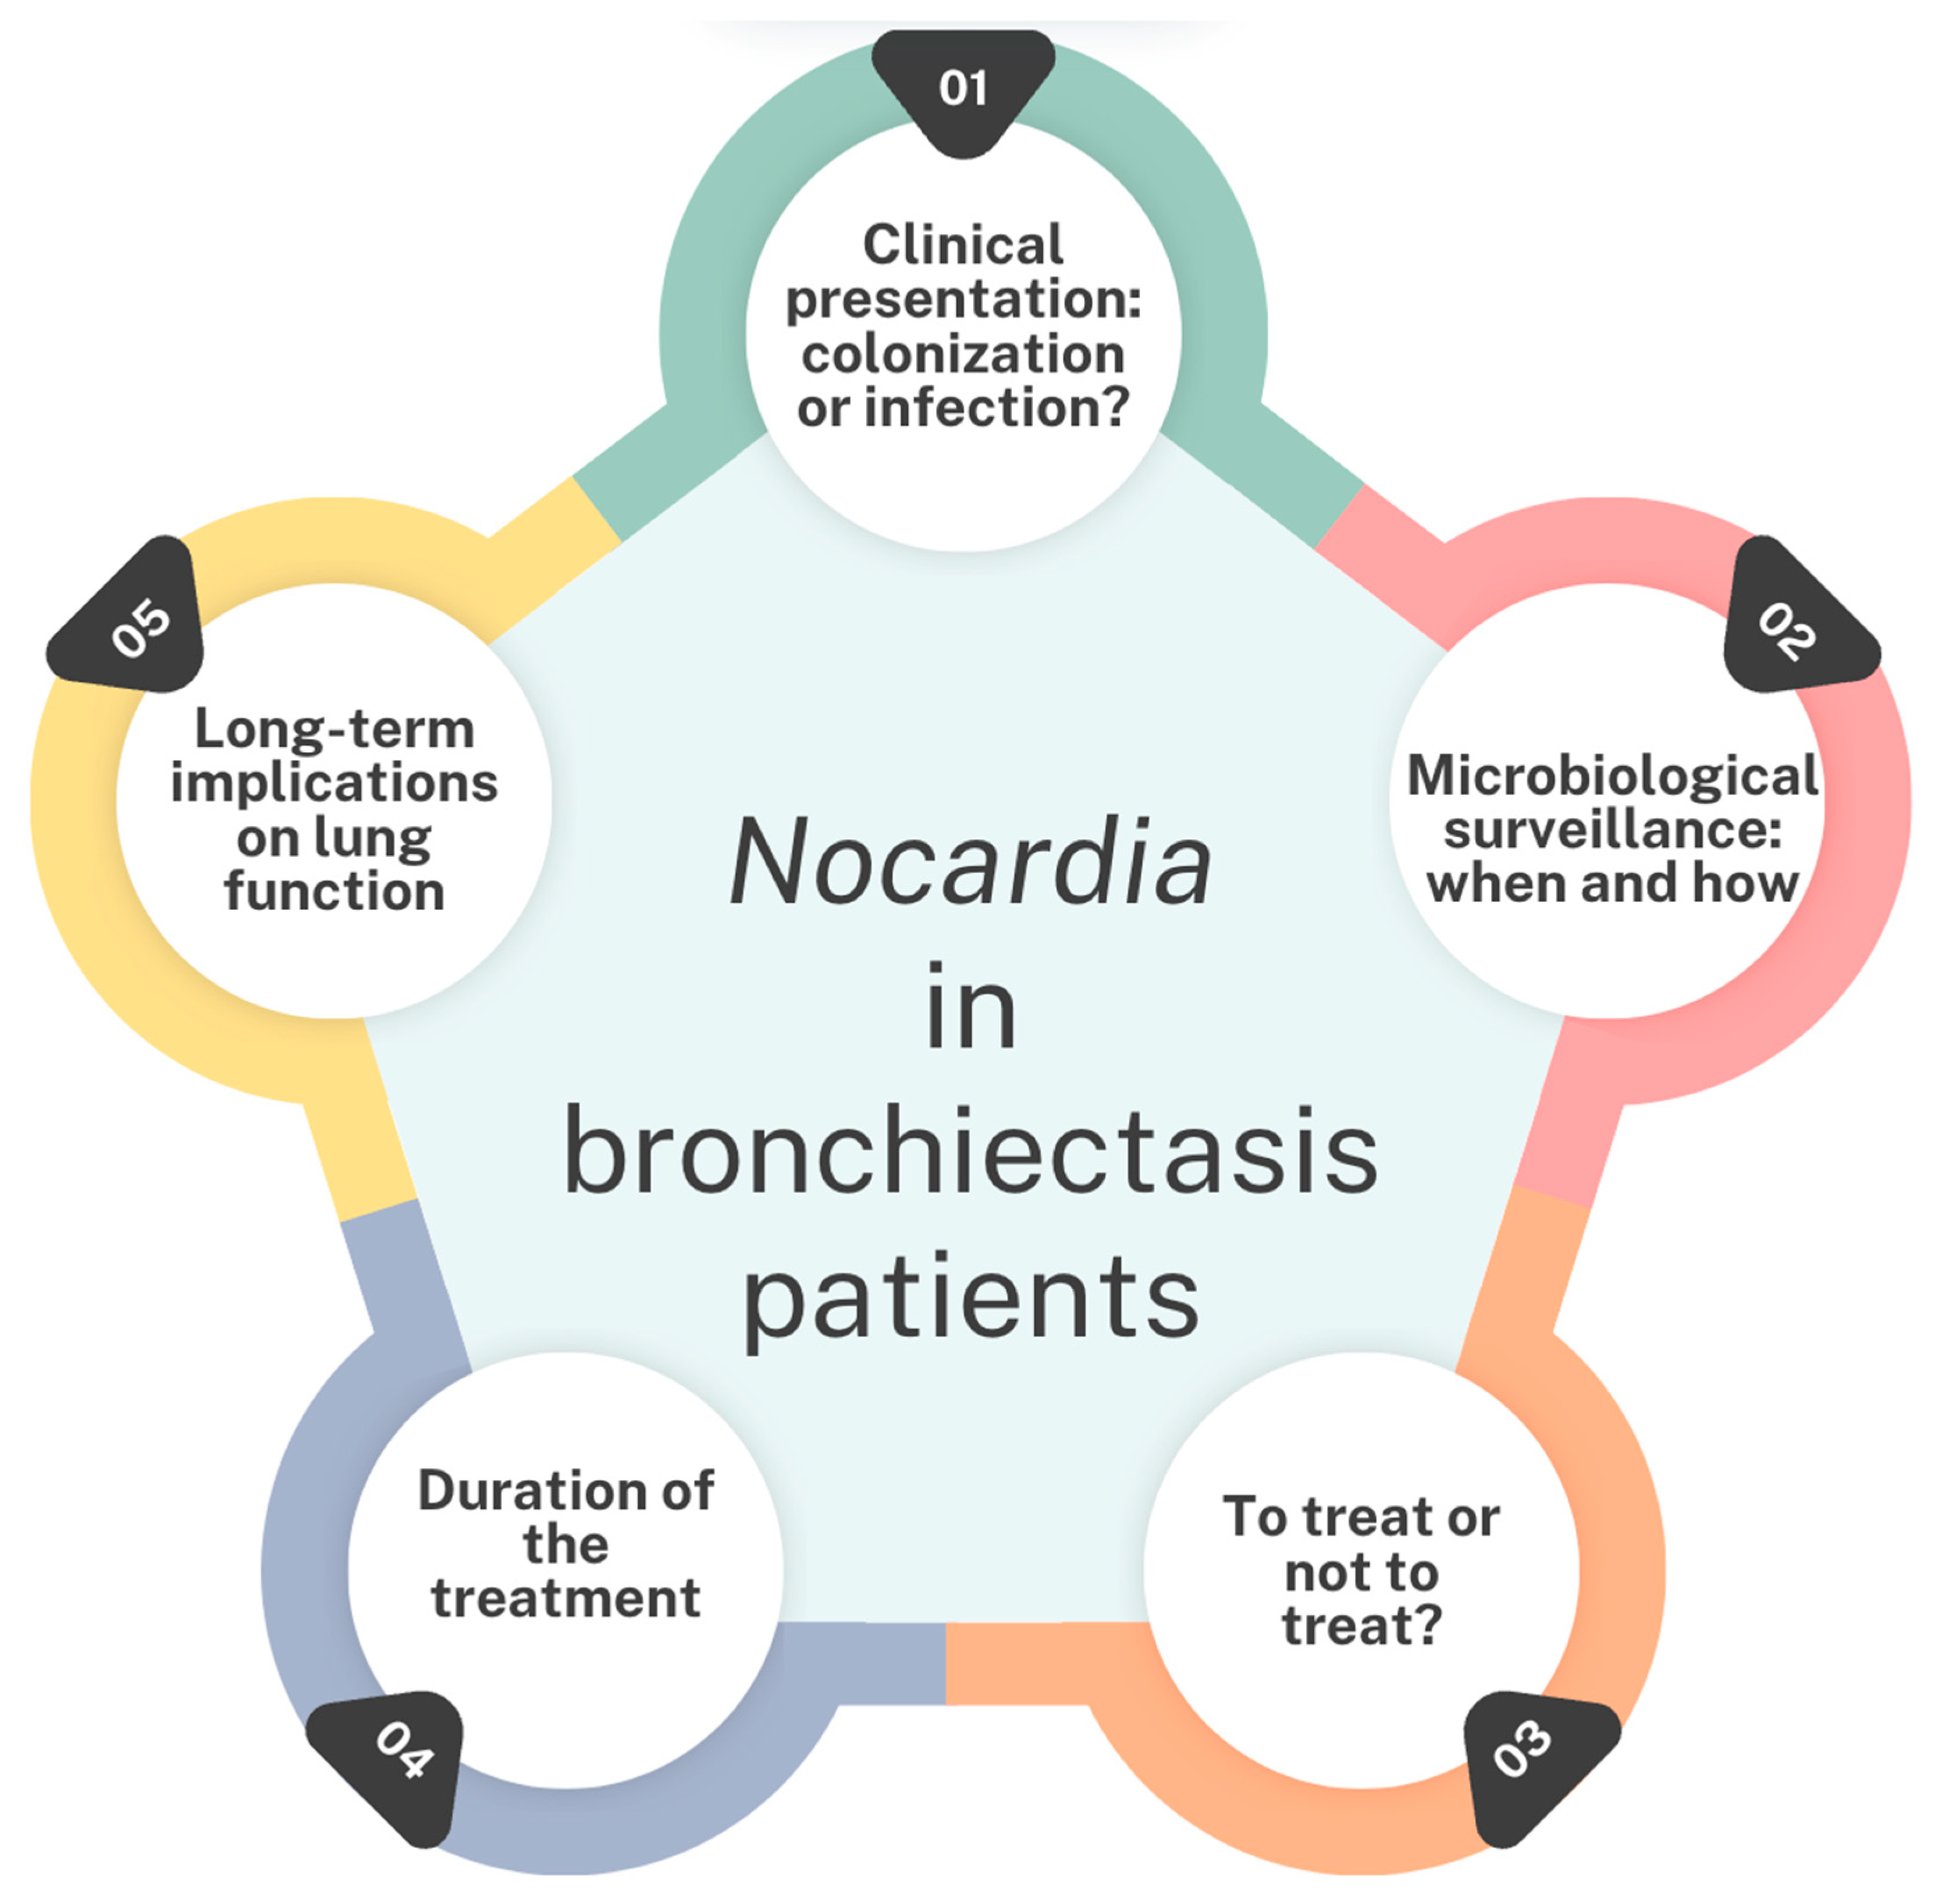

3. Discussion